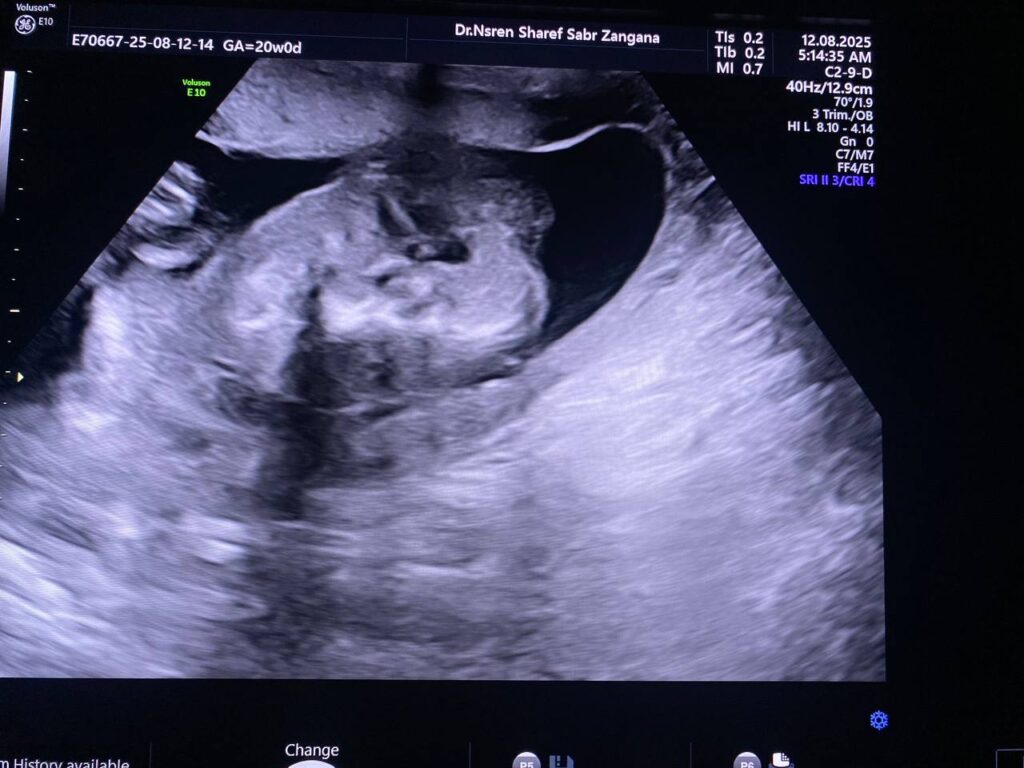

Multiple congenital anomaly seen , small chest , curve long bones , short limbs , kyphoscoliosis, congenital heart disease , edematous skin, picture mostly of thanatophoric dysplasia

F.L. = 16w+2d